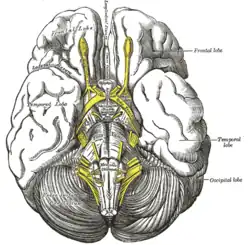

Anteroinferior view of the medulla oblongata and pons. Base of brain.